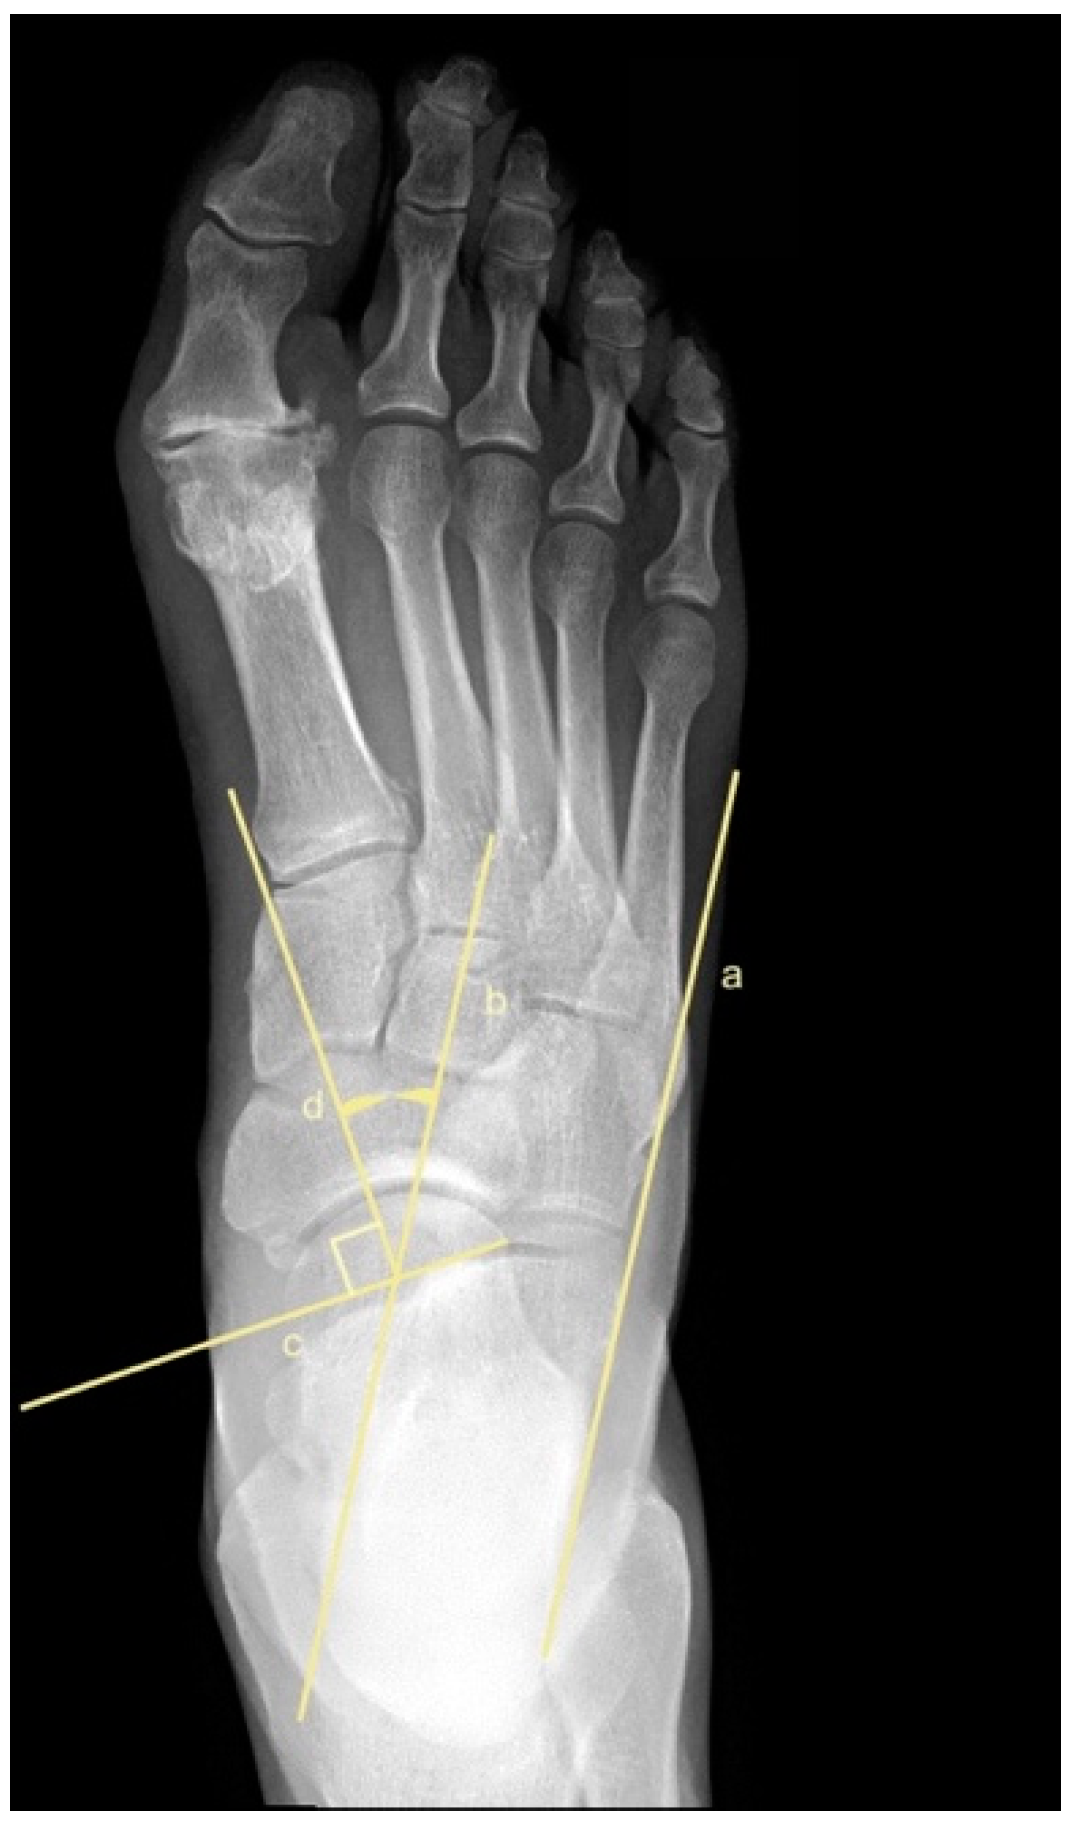

2.5. Metatarsus Adductus Measurements

- Simons, G.W. Analytical radiography of club feet. J. Bone Jt. Surg. Br. Vol. 1977, 59, 485–489. [Google Scholar] [CrossRef] [PubMed]

- Laaveg, S.J.; Ponseti, I.V. Long-term results of treatment of congenital club foot. J. Bone Jt. Surg. Am. Vol. 1980, 62, 23–31. [Google Scholar] [CrossRef]